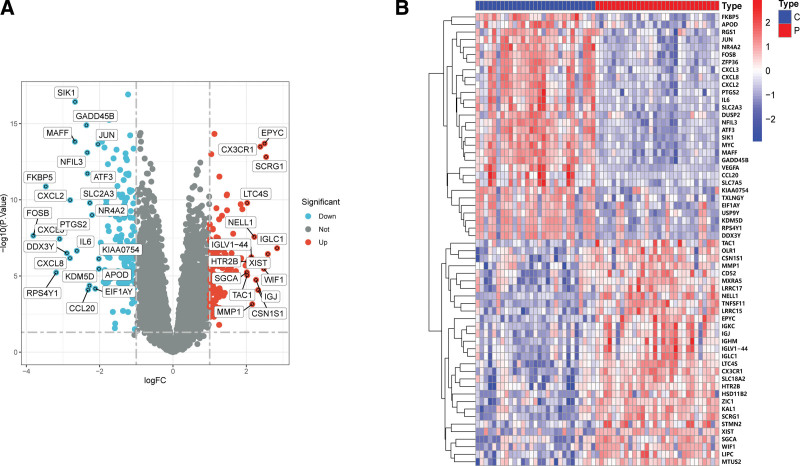

A total of 259 FRGs were identified. The entire analysis process of this study was presented in the Figure 1. At first, we compared the genes expression levels of normal control and OA disease group to identify DEGs. When comparing the synovial tissues of 30 OA patients and 29 normal controls, we found that 126 genes were highly expressed in OA samples while 156 genes were down-regulated. The results of DEGs were shown in the volcano plot and heatmap (Figs. 2A and 2B).

FerrDb is a database that is collected and managed manually containing integrated information ferroptosis-related genes. This study obtained 259 FRGs from the FerrDb database, including 186 ferroptosis driver genes, 132 suppressor genes and 113 ferroptosis marker genes. In this study, we screened 282 DEGs among which 126 were upregulated and 156 were downregulated. Results of followed GO enrichment analysis shown that all DEGs mainly associated with oxidative stress, steroid hormone, and muscle cell proliferation, while results of KEGG enrichment analysis indicated that DEGs were closely related to IL-7 signaling pathway, TNF signaling pathway, HIF-1 signaling pathway, Human T-cell leukemia virus 1 infection, and NOD-like receptor signaling pathway. These findings suggested that DEGs play roles in inflammatory process in OA, suggesting possible impact of these genes’ occurrence and development of OA. We subsequentially performed Venn plot to selected the ferroptosis-related hub genes in OA with the intersection of FRGs and DEGs.